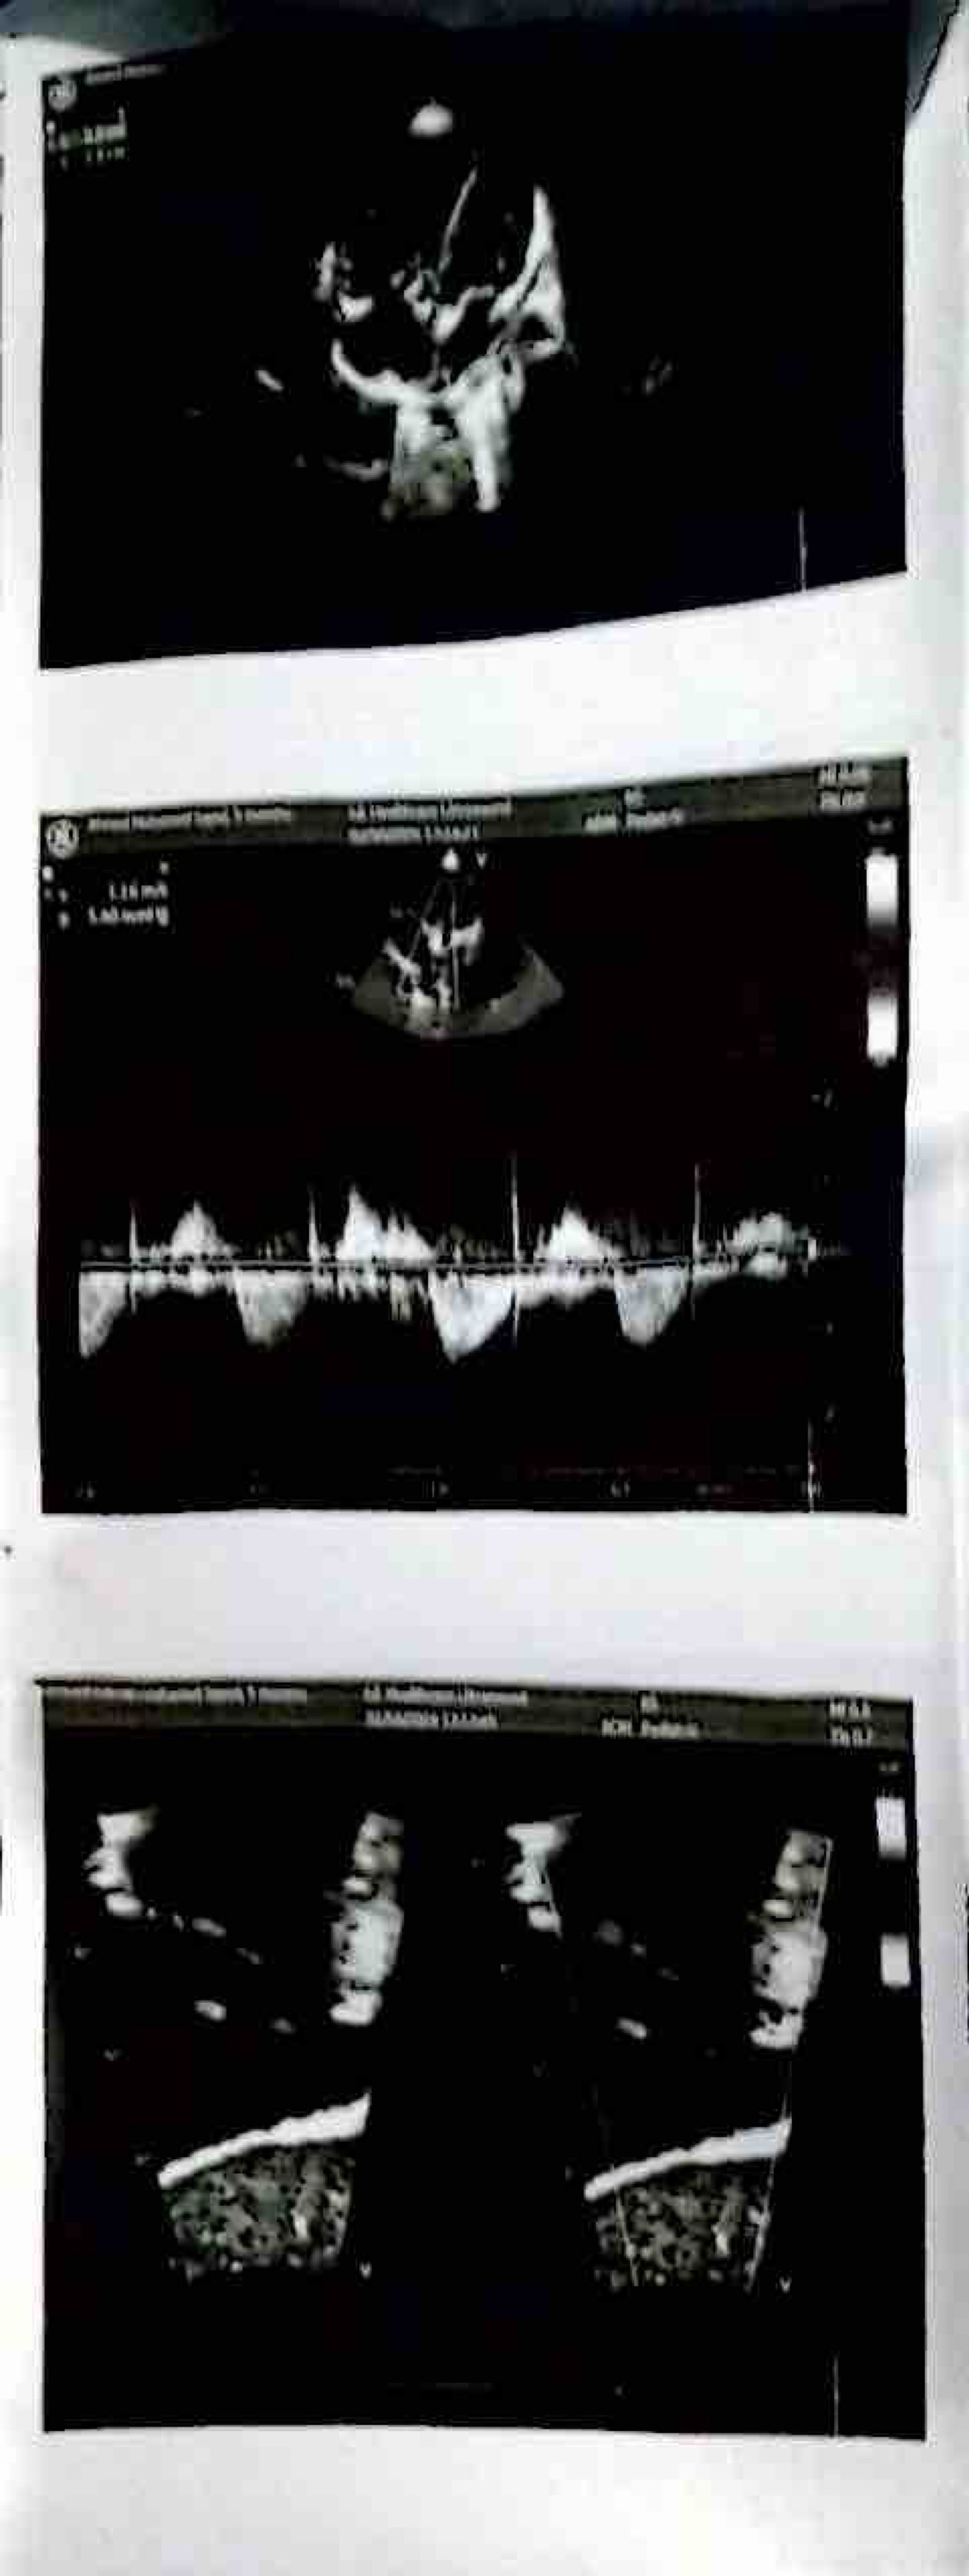

My name is Fahad and I’m looking to help my colleague who is fundraising for her friend in Egypt whose 15 month old child Ahmed is currently suffering from a heart abnormality.